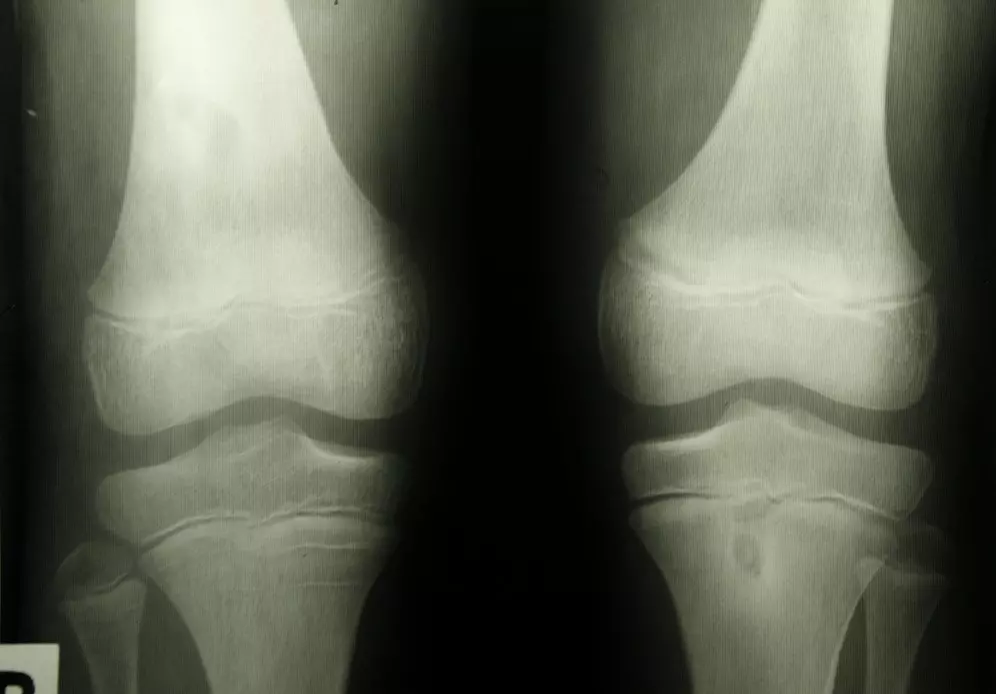

Uszkodzenie chrząstki stawowej

Państwa uwadze polecamy tekst pt. „Uszkodzenia chrząstki stawowej przedziału rzepkowo-udowego”. Lek. med. Piotr Zamojcin wskazuje, że „staw rzepkowo-udowy stanowiący jeden z dwóch stawów tworzących staw kolanowy często jako pierwszy daje objawy podczas tworzących się zmian zwyrodnieniowych. Przenosząc znaczne przeciążenia podczas pracy aparatu wyprostnego kolana narażany jest w dużej mierze na uszkodzenia”. W tekście omawia on schorzenia, które najczęściej występują w przedziale rzepkowo-udowym. Autor wskazuje także na etapy, w jakich przebiega uszkodzenie chrząstki stawowej.